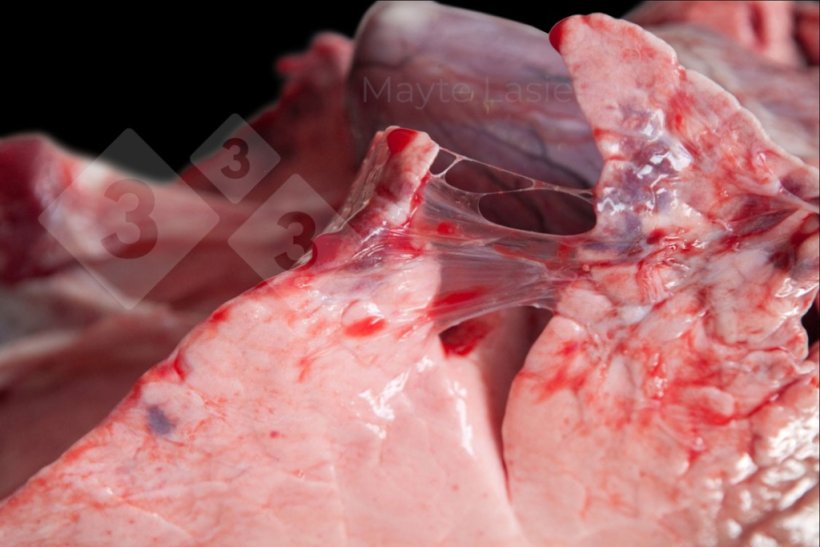

Les pleurésies sont fréquentes et sont des lésions qui touchent la région dorso-caudale du poumon, principalement associées aux formes subaiguës ou chroniques de la pleuropneumonie porcine (APP). Elles se manifestent sous forme de zones blanchâtres sur la plèvre viscérale des lobes diaphragmatiques, qui correspondent à des dépôts de fibrine.

Pleurésie dorsocaudale

Pleurésie dorsocaudale